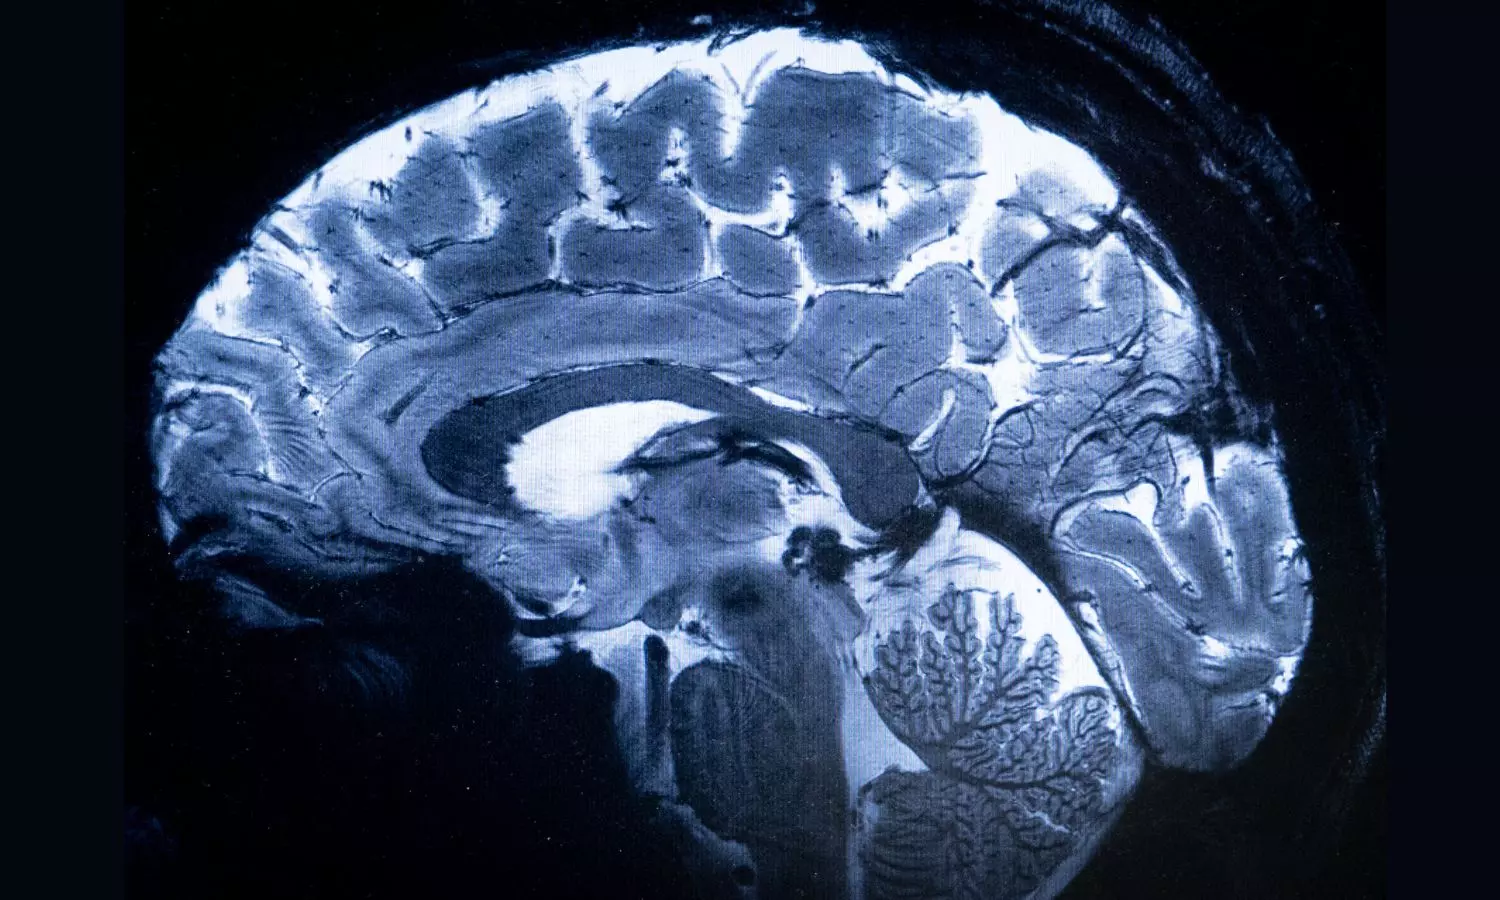

China Joins US In Brain Implant Race With Clinical Trial. (Photo: Bloomberg)

China’s first clinical trial of a technology that allows signals from the brain to control an external device has proved successful, making it only the second country after the US to reach this stage, according to the Global Times.

Chinese researchers used brain-computer interfaces, or BCI, a wireless invasive implant in a patient with tetraplegia in March, the English-language newspaper reported. Only a few weeks after the surgery, the patient was able to play racing games and chess on the computer using only the mind to control the electronic devices, it said, citing a statement from the Shanghai-based Center for Excellence in Brain Science and Intelligence Technology.

BCI is an emerging technology to help restore functionality to people with paralysis, and Neuralink Corp., co-founded by Elon Musk, is at the forefront of this research. The implant used in the Chinese trial is the world’s smallest so far, with a diameter of 26 millimeters and thickness less than 6 millimeters, the Global Times said, adding that it’s over 100 times more flexible than the one developed by Neuralink.